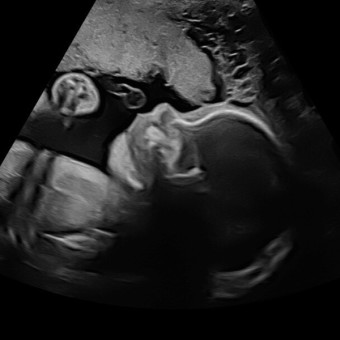

Ashley & Rob's Baby Registry

Ashley & Rob Reed

Utica, NY

December 2, 2025

Thank you everyone for visiting our rainbow babies registry!